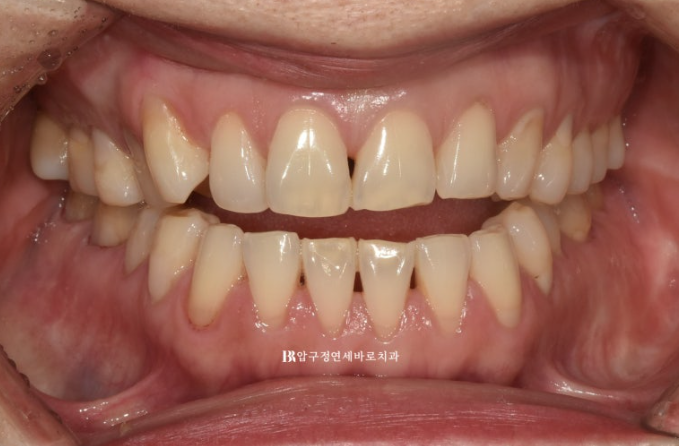

올해 5월 개방교합 때문에 찾아오신 50대 환자분입니다.

위 어금니를 뼛속으로 밀어올리는 함입교정이 필요함을 설명드렸습니다.

23.05

클리피씨나 인비절라인이나 비슷한 기간에 비슷한 효과를 볼 수 있으니 장치 선택은 편하게 하시도록 설명도 드렸습니다.

환자분은 심미적인 이유로 인비절라인 선택하셨습니다.

첫번째 작은어금니까지 8개 치아는 떠있고 두번째 작은어금니부터 큰어금니까지 3개씩 닿아있는 상태입니다.

이런 상태에서는 닿고있는 위 어금니 3개씩 총 6개 치아를 함입시키는 치료계획으로 진행합니다.